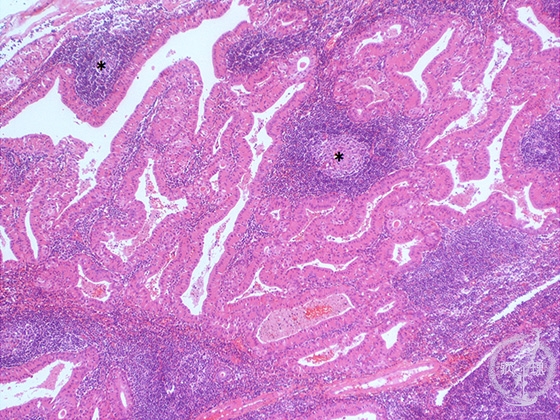

- 7.Oral, Salivary gland

- (7)Salivary gland tumor(★Warthin tumor)

Microscopic finding (HE stain, low-power view):The eosinophilic tumor cells lining the cystic spaces form papillary processes which protrude into the cysts. The stroma includes lymphoid tissue with follicle formation (*).